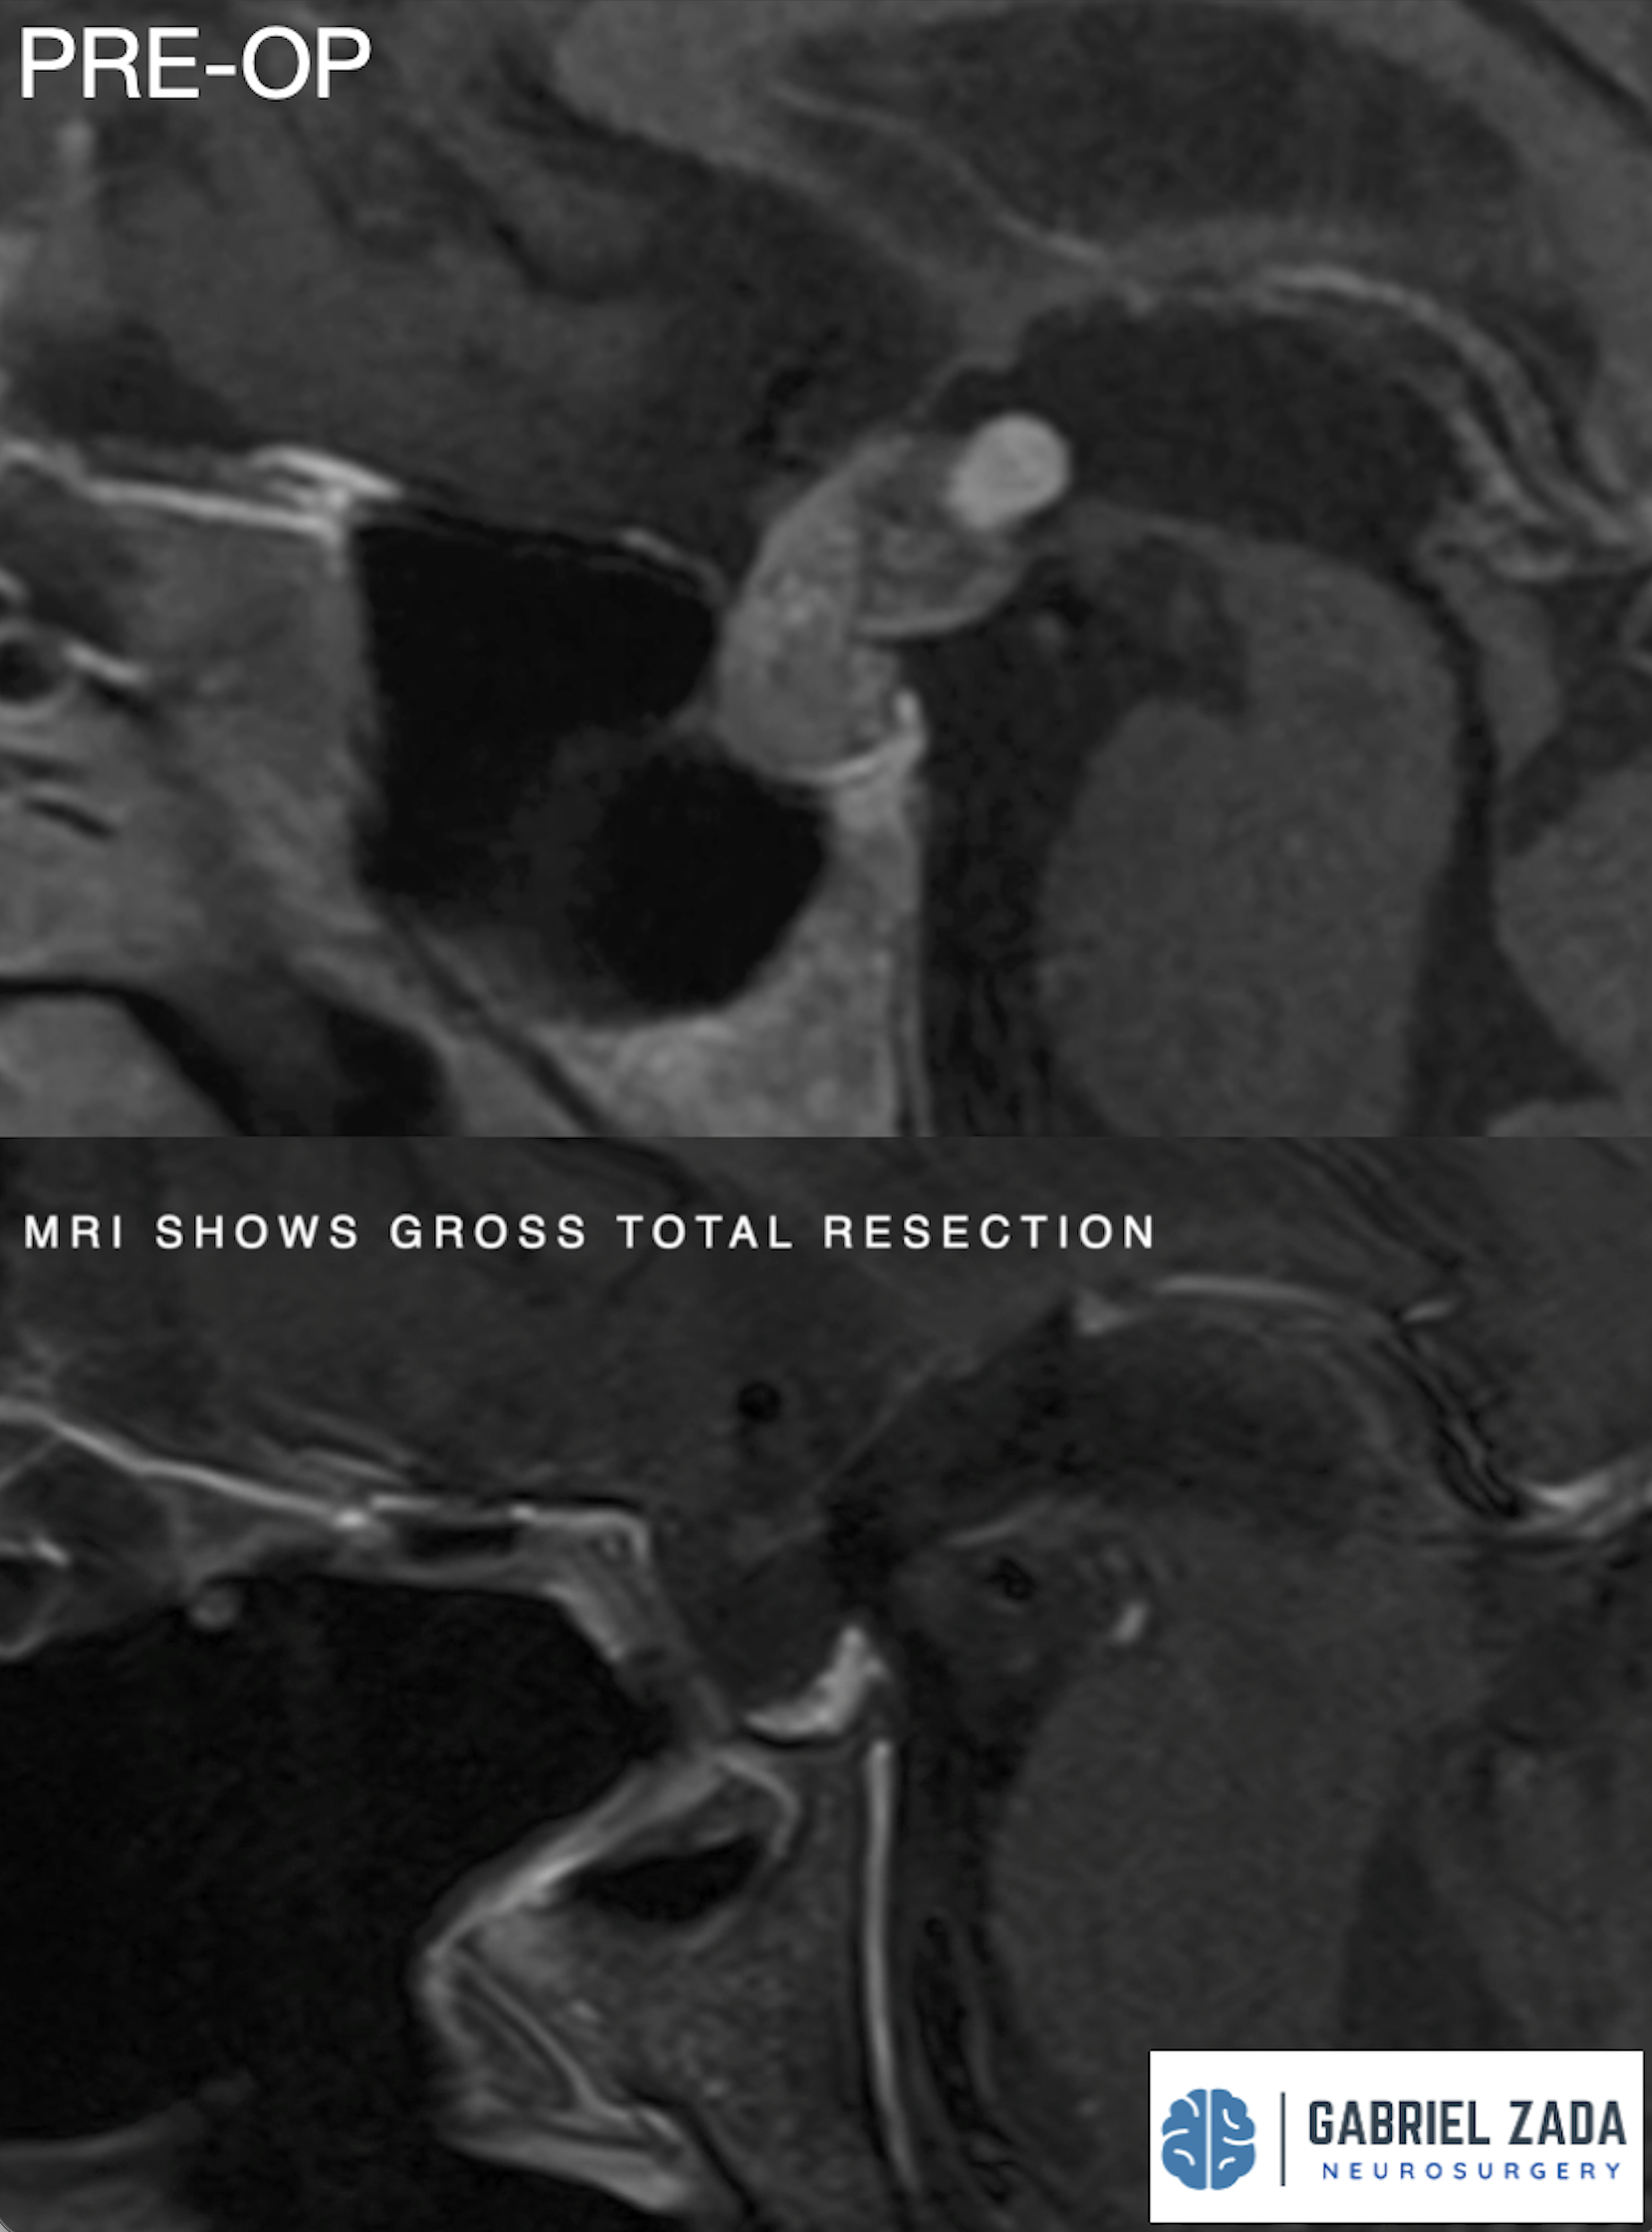

Explore this comprehensive gallery featuring pre‑ and post‑operative imaging of patients with skull‑base tumors treated by Gabriel Zada, MD, MS, FAANS, FACS. These cases highlight Dr. Zada’s expertise in advanced neurosurgical techniques and outcomes.

*Representative cases shown for educational purposes. All images de-identified. Individual results vary.